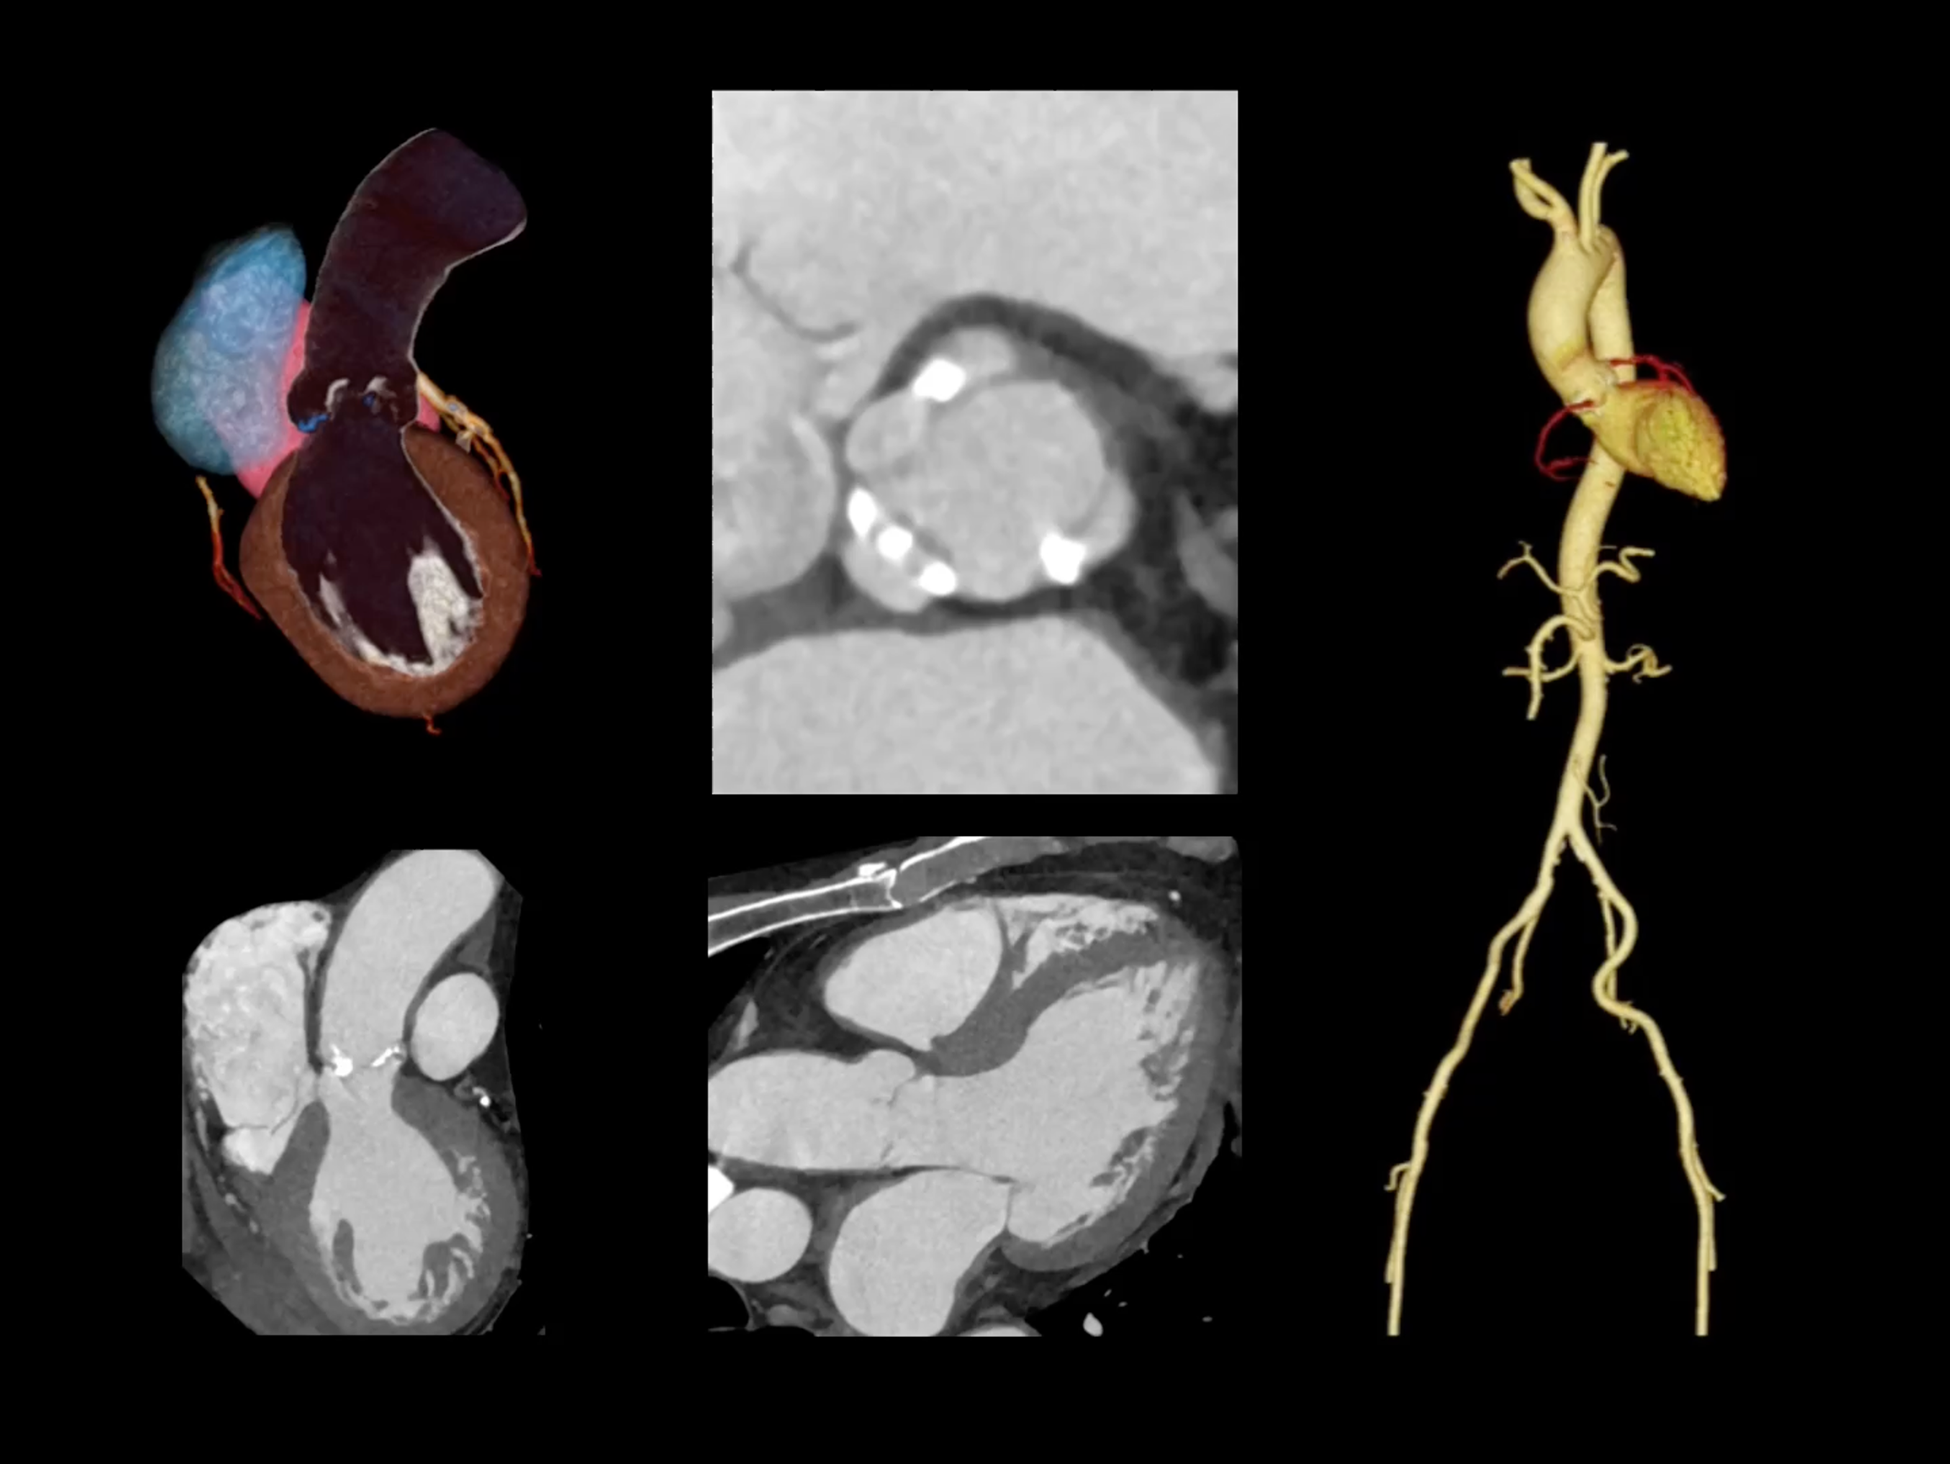

全域能谱

uCT SiriuX® 依托16cm超宽探测器与双源能谱技术,实现真正意义上的全身高清能谱成像。单次扫描同步获取灌注、能谱等多维定量参数,精准解析组织特性与病灶成分,为临床决策提供更深层次的诊断依据。

全身高清能谱成像

uCT SiriuX® 采用独有的双宽体探测器设计,实现470mm超大视野与全脏器容积覆盖的能谱成像,轻松应对不同体型患者和扫描部位应用需求。配合创新能谱重建影像链与精准双能数据配准,系统可有效抑制伪影、提升信噪比,在全脏器范围内提供高质量能谱图像,显著拓展临床精准诊断的广度与深度。

470 mm

• 双宽大视野

• 支持全身各部位能谱成像

SpeX

• 双能高精配准与硬化伪影校正

• 高清能谱分解&降噪重建技术

• 支持全身各部位、各类能谱成像

全面能谱分析工具

能谱成像可揭示丰富的物质与能量信息,其临床价值的充分释放有赖于完善高效的后处理分析平台。uCT SiriuX® 提供全面能谱高级分析工具,覆盖心血管、肿瘤、神经、骨科等多类临床场景。平台支持动脉增强分数分析(AEF)、细胞外容积分析(ECV)、肿瘤同源性分析、肺栓塞分析、骨髓水肿分析等多项评估,并提供多达10种基物质对成像,为精准诊断与科研探索提供坚实支撑。